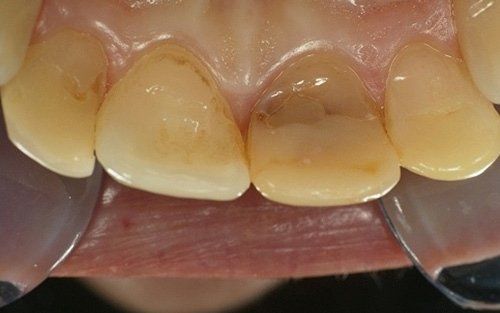

Qui raffigurato l'incisivo laterale di destra, dopo la rimozione del vecchio restauro.

Il restauro definitivo sul dente laterale: notare la buona integrazione fra il dente e il restauro.

Il laterale di sinistra dopo la rimozione del vecchio restauro. Anche in questo caso tutto il tessuto sano della paziente è stato mantenuto.

Il laterale di sinistra ultimato.